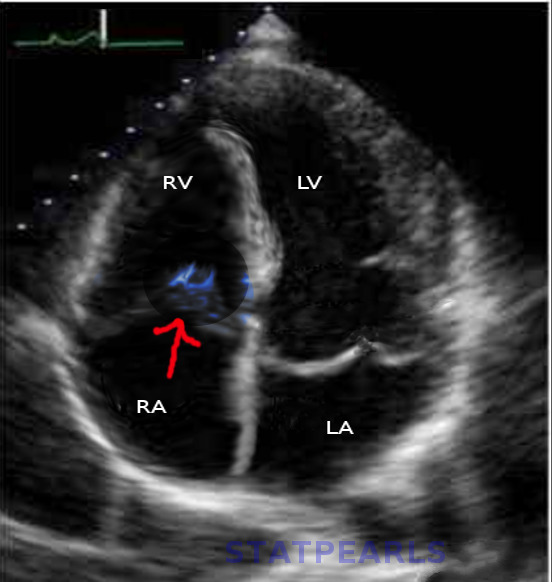

Contributors: Preeya Prakash MD, Adam Greenhaw PharmD, Travis Barlock MD, and Jeffrey Olson MS4 In this episode, cardiologist Preeya Prakash and medical student Jeffrey Olson listen in as two cases are presented from EMM's recent event, Tox Talk 2025. Talk 1- Digoxin Overdose Dr. Adam Greenhaw presents a case of a Digoxin overdose along with many pearls. During the studio listen in, Dr. Prakash helps to answer the questions of: How does digoxin work? Why might a patient still be on digoxin in 2025? What are the EKG findings of digoxin toxicity? Is there any utility in atropine for bradycardia caused by digoxin? Should you use calcium to treat hyperkalemia in the setting of a digoxin overdose? If/when might a cardiologist get involved in a patient with a digoxin overdose? Talk 2- Propranolol Overdose Dr. Travis Barlock presents a case of a beta blocker overdose as well as many associated pearls. During our studio listen in, Dr. Prakash helps to answer the questions of: What are the different beta blockers and how do they work? If you are worried about a propranolol overdose, what medications do you want on hand? What POCUS cardiac view can give you the most information for different scenarios? Why or why not might transcutaneous or intravenous pacing be a good idea for a beta blocker overdose? If/when might you want a cardiologist to get involved in a patient with a beta blocker overdose? References Alahmed AA, Lauffenburger JC, Vaduganathan M, Aldemerdash A, Ting C, Fatani N, Fanikos J, Buckley LF. Contemporary Trends in the Use of and Expenditures on Digoxin in the United States. Am J Cardiovasc Drugs. 2022 Sep;22(5):567-575. doi: 10.1007/s40256-022-00540-x. Epub 2022 Jun 24. PMID: 35739347; PMCID: PMC10263277. Chan BS, Buckley NA. Digoxin-specific antibody fragments in the treatment of digoxin toxicity. Clin Toxicol (Phila). 2014 Sep-Oct;52(8):824-36. doi: 10.3109/15563650.2014.943907. Epub 2014 Aug 4. PMID: 25089630. Hack JB, Wingate S, Zolty R, Rich MW, Hauptman PJ. Expert Consensus on the Diagnosis and Management of Digoxin Toxicity. Am J Med. 2025 Jan;138(1):25-33.e14. doi: 10.1016/j.amjmed.2024.08.018. Epub 2024 Sep 11. PMID: 39265879. Krenz JR, Kaakeh Y. An Overview of Hyperinsulinemic-Euglycemic Therapy in Calcium Channel Blocker and β-blocker Overdose. Pharmacotherapy. 2018 Nov;38(11):1130-1142. doi: 10.1002/phar.2177. Epub 2018 Oct 4. PMID: 30141827. Patocka J, Nepovimova E, Wu W, Kuca K. Digoxin: Pharmacology and toxicology-A review. Environ Toxicol Pharmacol. 2020 Oct;79:103400. doi: 10.1016/j.etap.2020.103400. Epub 2020 May 7. PMID: 32464466. Rotella JA, Greene SL, Koutsogiannis Z, Graudins A, Hung Leang Y, Kuan K, Baxter H, Bourke E, Wong A. Treatment for beta-blocker poisoning: a systematic review. Clin Toxicol (Phila). 2020 Oct;58(10):943-983. doi: 10.1080/15563650.2020.1752918. Epub 2020 Apr 20. PMID: 32310006. Produced by Jeffrey Olson, MS4 Donate: https://emergencymedicalminute.org/donate/